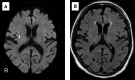

Patient concerns and diagnoses: We evaluated patients who recovered from COVID-19 and showed acute disturbance of consciousness or focal neurological deficits without recurrence of pneumonitis. Six patients, 2 females and 4 males, with ages ranging from 65 to 83 years were included. Durations of hospitalization due to COVID-19 were between 25 and 44 days. The severity of COVID-19 was moderate in 5 and severe in 1 patient. Patients were rehospitalized for acute disturbance of consciousness concomitant with postural tremor and, abnormal behavior, hemiplegia, aphasia, or apraxia between 34 and 67 days after the onset of COVID-19. Chest computed tomography showed no exacerbation of pneumonitis. Brain magnetic resonance imaging showed no specific findings except in 1 patient with an acute lacunar infarction. Electroencephalogram demonstrated diffuse slowing in all patients. Repeat electroencephalogram after recovery from encephalopathy demonstrated normal in all patients. One of the 6 patients had cerebrospinal fluid (CSF) pleocytosis. CSF protein levels were elevated in all patients, ranging from 51 to 115 mg/dL. CSF interleukin-6 levels ranged from 2.9 to 10.9 pg/mL. The immunoglobulin index was 0.39 to 0.44. Qlim(alb) < QAlb indicating dysfunction of the blood-brain barrier was observed in all patients. Severe acute respiratory syndrome coronavirus 2 reverse transcription polymerase chain reaction of CSF was negative in all patients. Neuronal autoantibodies were absent in serum and CSF.